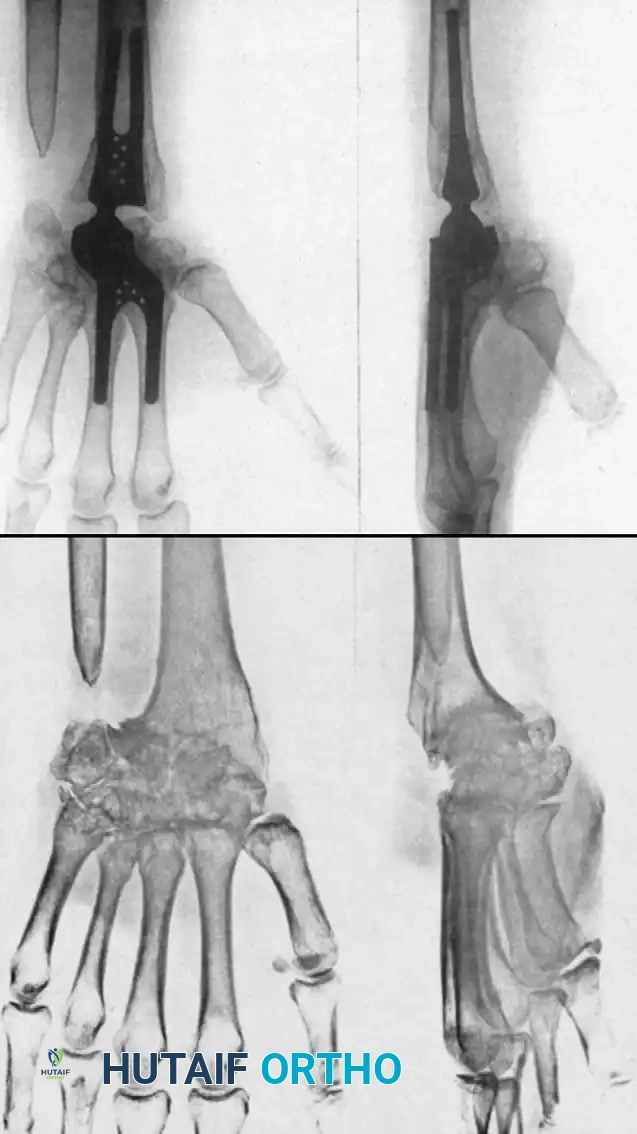

Silicone Implant Arthroplasty (Swanson)

Silicone spacer arthroplasty remains a viable option for low-demand rheumatoid patients with advanced disease (Stage III or IV) and poor bone stock that precludes the use of metal-on-plastic total wrist systems. The procedure requires minimal bone resection and acts as a dynamic spacer to maintain alignment while a fibrous capsule forms.

Image

Total Wrist Arthroplasty (TWA)

Total joint arthroplasty offers the distinct advantages of preserving functional motion, providing a fixed fulcrum for tendon excursion, and achieving stable fixation. Modern designs are generally semi-constrained to allow for physiologic kinematics while preventing dislocation.

Implants such as the Meuli, Volz, and Biaxial wrist prostheses have shown excellent early to mid-term results in pain relief and motion preservation. However, the Achilles heel of TWA remains distal component loosening. The carpal bones in RA are often osteopenic and cystic, providing poor purchase for the distal pegs or screws.

Complications, including distal loosening, subsidence, and periprosthetic fracture, lead to an overall revision rate of 9% to 35%. Adequate muscle balance, correctable preoperative wrist contractures, and meticulous surgical technique are absolute prerequisites for a successful TWA.